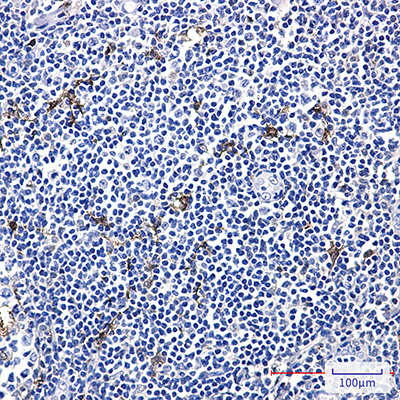

WB,IHC-P,IP

稀释比(Dilution Ratio)

WB: 1:500-1:1000 IHC: 1:50-1:100 IP: 1:20